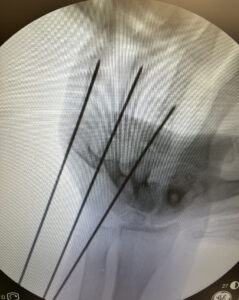

A técnica abaixo, utilizada em fraturas muito proximais de falange proximal na qual o fio de Kirschner é passado através da cabeça do metacarpo é conhecida como técnica de:

Qual é essa técnica?